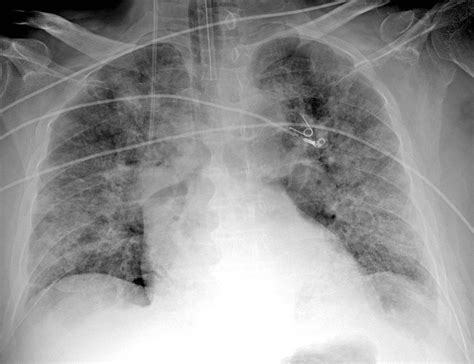

Pneumonia is an infection that inflames the air sacs (alveoli) in one or both lungs. When these air sacs fill with fluid or pus, they appear denser than the surrounding healthy air-filled lung tissue on an X-ray. Radiologists look for specific patterns of opacity, often referred to as infiltrates or consolidations, to confirm a diagnosis of pneumonia on CXR.

The appearance of pneumonia can vary significantly depending on the causative organism, the patient's immune status, and the timing of the imaging. Generally, radiologists categorize these findings into several distinct patterns:

• Lobar Consolidation: This is the classic appearance of bacterial pneumonia, such as that caused by Streptococcus pneumoniae. A defined portion of a lung lobe appears white (opaque) due to the consolidation of fluid, often featuring air bronchograms—dark, branching lines representing air-filled bronchi surrounded by consolidated alveoli.

• Bronchopneumonia (Patchy Opacities): Common in hospital-acquired infections or atypical pathogens, this pattern presents as scattered, poorly defined opacities throughout one or both lungs, rather than being confined to a single lobe.

• Interstitial Infiltrates: Often associated with viral or atypical pneumonia (such as Mycoplasma pneumoniae), this appears as fine, lace-like (reticular) markings throughout the lungs, focusing on the interstitial space rather than the alveoli.